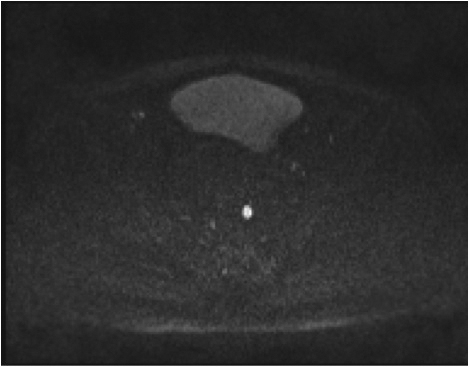

Fig1. Pacient cu neoplasm rectal stadiul IIIC (T3; N2; M0) confirmat bioptic, adenocarcinom mixt G2

a-d imagini T2 ponderate în plan sagital, oblic axial și oblic coronal – masă tisulară dezvoltată superior de joncțiunea anorectală, lateral dreapta, cu minimă extensie la nivelul grăsimii mezorectale și limfoganglioni mezorectali cu diametru de până la 10 mm;

e,f) restricție de difuzie la nivelul tumorii rectale și a doi ganglioni mezorectali

g,h,i) priză de contrast moderată la nivelul tumorii rectale și al ganglionilor mezorectali

j) reconstrucții curbe în planul adevărat al rectului, cu evidențiere mai bună a fasciei mezorectale